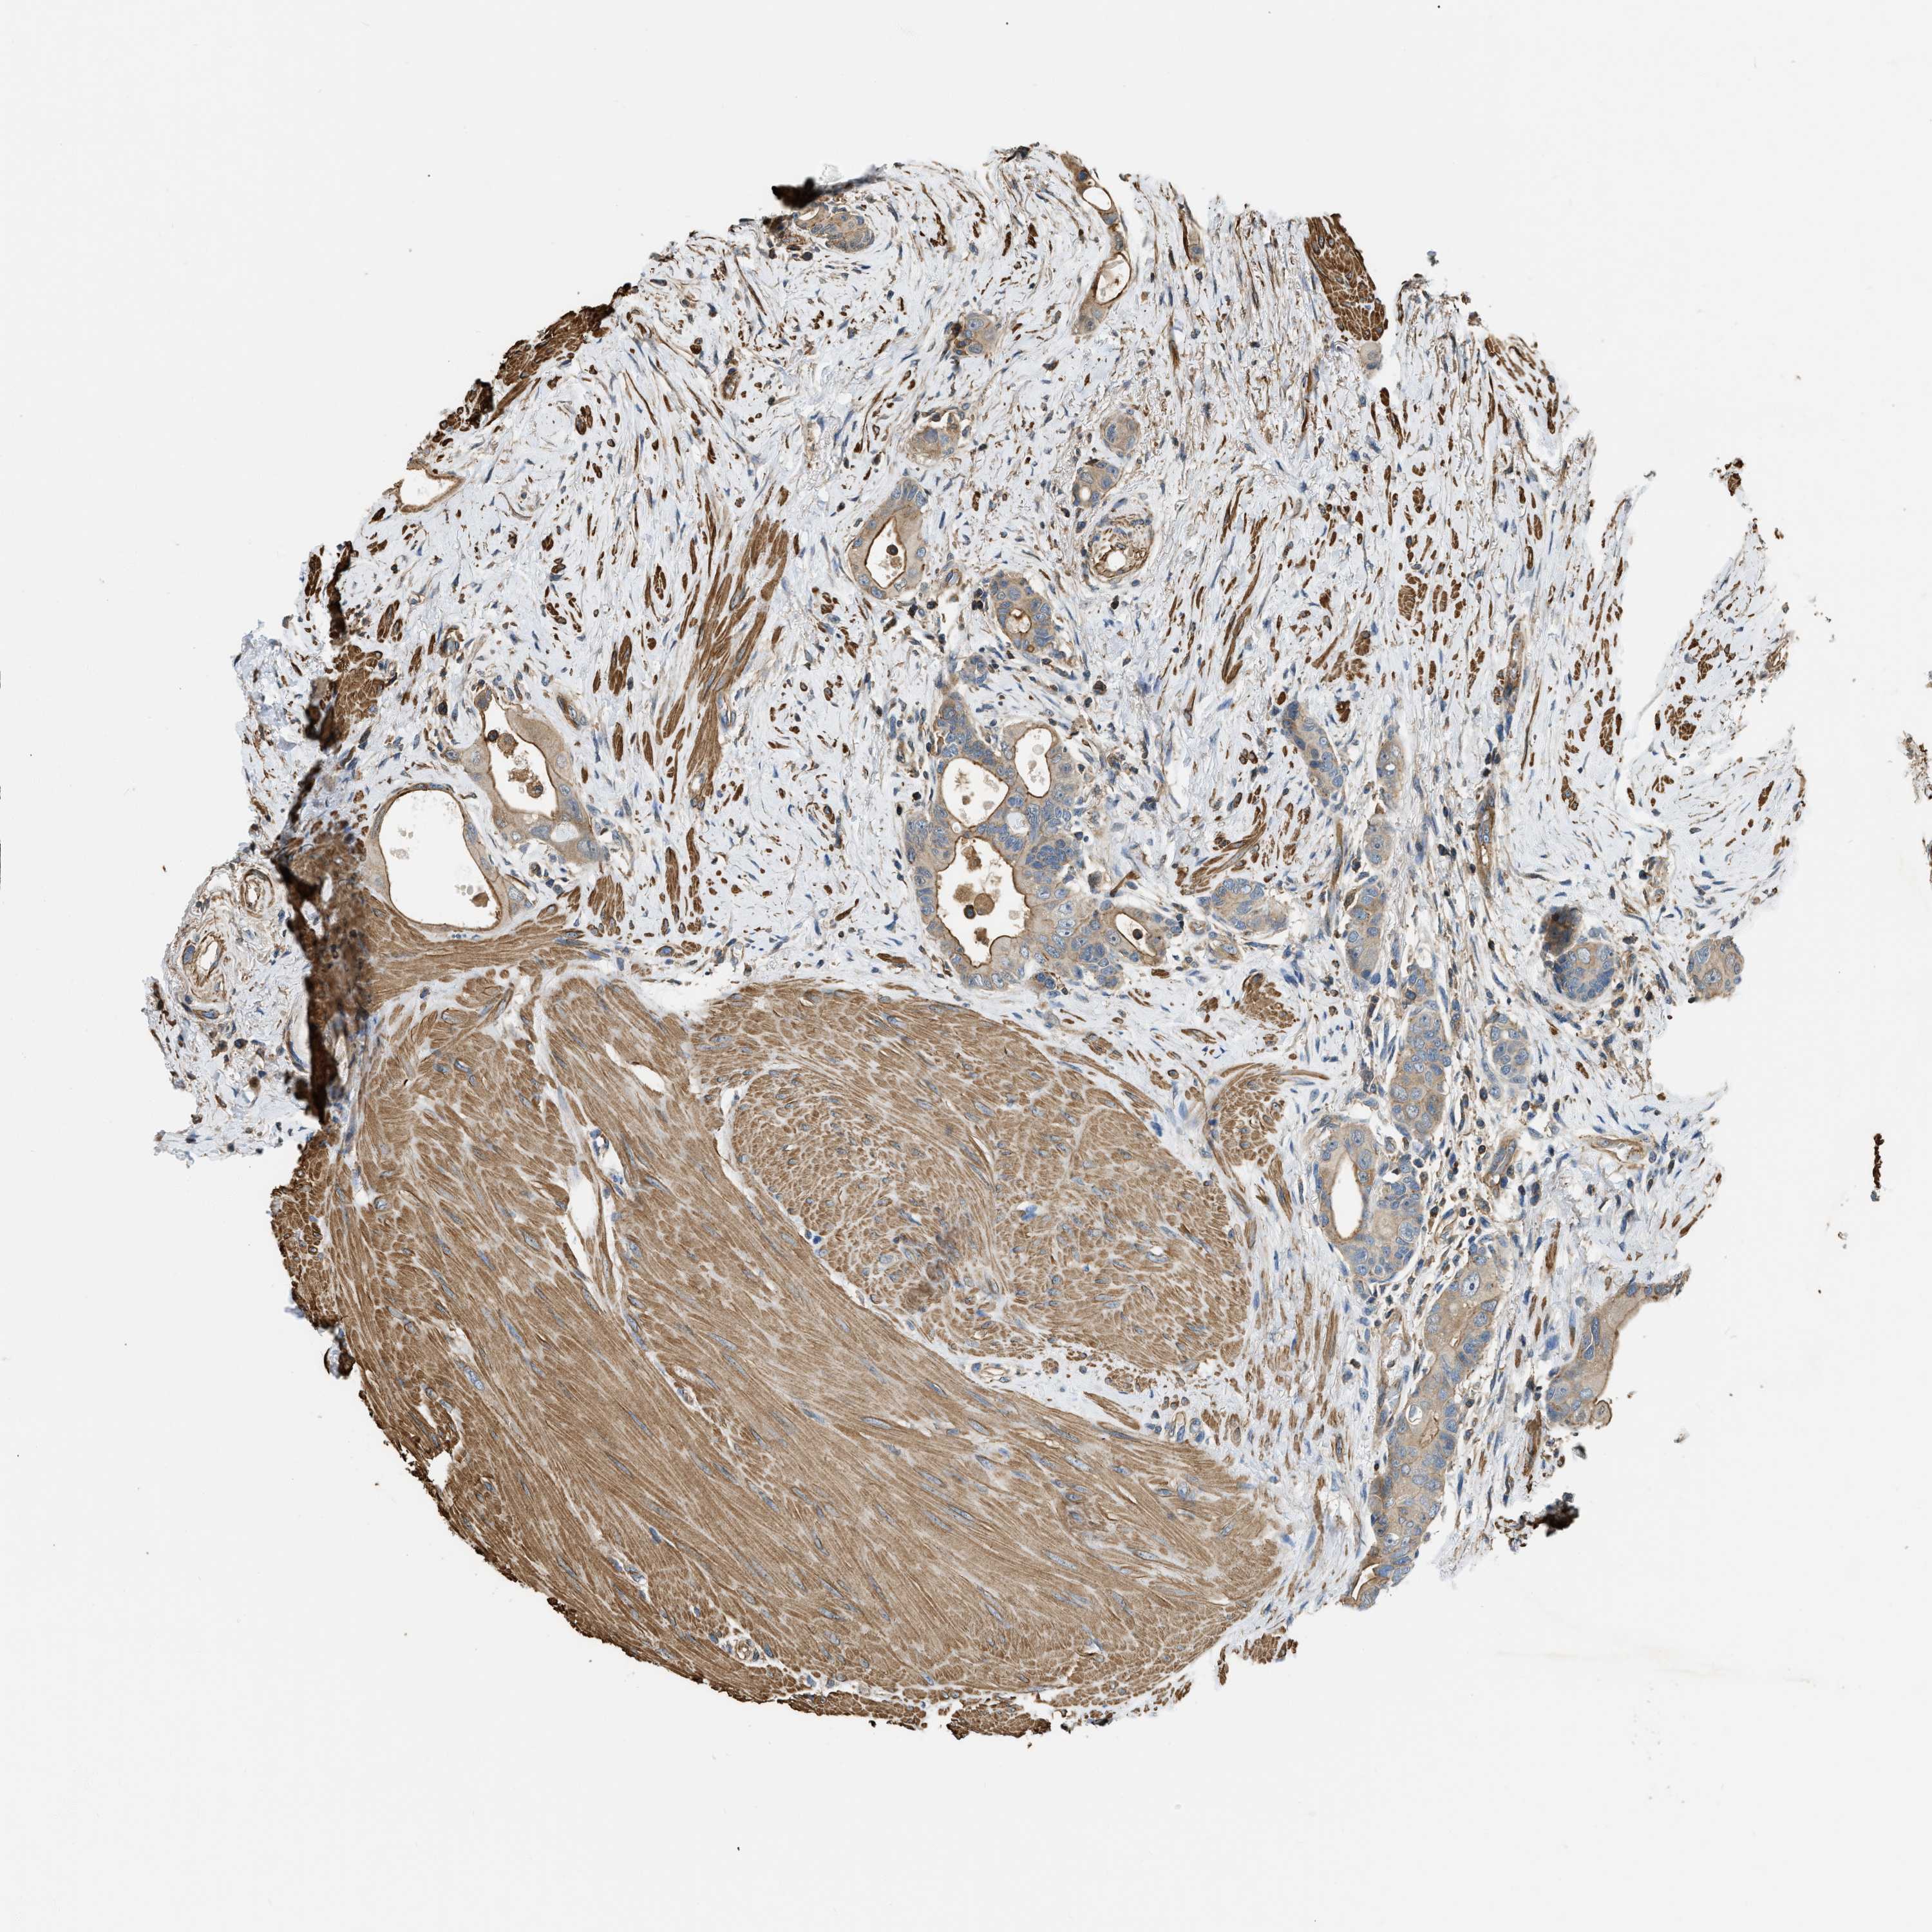

CANCER COLORECTAL CANCER Show tissue menu

COAD TCGA COAD VALIDATION READ TCGA READ VALIDATION PROTEIN COAD CPTAC PROTEIN EXPRESSION

ANTIBODIES

AND

VALIDATION